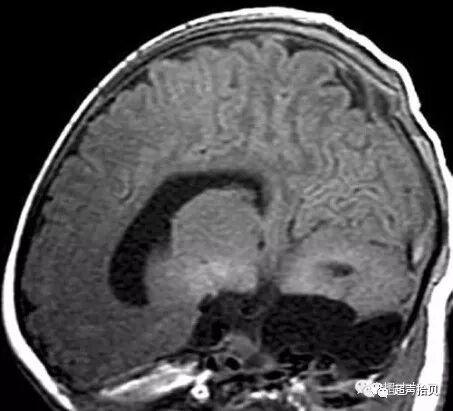

图3:位于颞窝的蛛网膜囊肿(C)。A:26周妊娠时横向超声扫查获得囊肿图像,彩色多普勒超声检查显示囊肿中没有流动。 B,28孕周产前核磁共振显示囊肿(C)位于颞侧窝(T2加权像[T2WI],横向平面)。 C,出生后1个月的产后MRI证实囊肿。(T2加权像[T2WI],横断面)